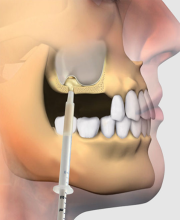

1. کیفیت بالا و نتایج ماندگار:

در مرکز تخصصی دکتر محمودی، از بهترین مواد و تکنولوژیهای روز دنیا برای انجام ایمپلنت دندان استفاده میکنیم. شما میتوانید مطمئن باشید که نتیجه کار دائمی و با کیفیت خواهد بود.

3. راحتی در درمان:

ایمپلنت دندان فرآیندی ساده است که با تکنولوژیهای پیشرفته ما، بدون درد و با حداقل زمان به نتیجه میرسد.

مرکز تخصصی دکتر محمودی با بیش از سالها تجربه در ارائه خدمات دندانپزشکی پیشرفته، به شما این اطمینان را میدهد که درمان شما با بهترین کیفیت و در محیطی کاملاً استریل و بهداشتی انجام خواهد شد. پزشکان ما از تکنیکهای نوین و تجهیزات روز دنیا برای انجام ایمپلنت استفاده میکنند.